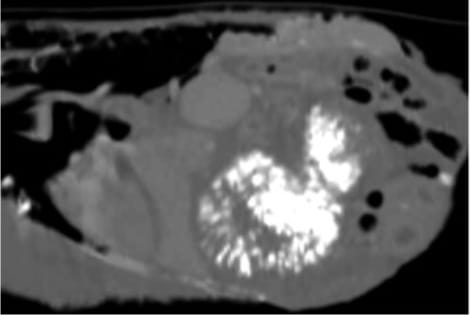

Contrast computed tomography sagittal section of an Eclectus parrot with disseminated xanthogranulomatosis with extensive calcification of the ventriculus and other coelomic structures. Bile acids were also elevated. The bird was treated with prednisolone.